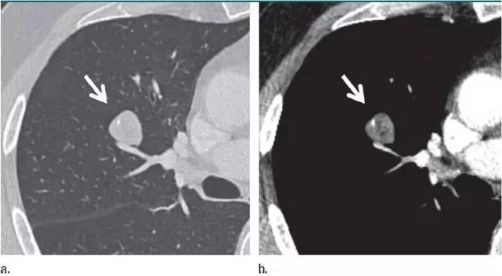

重磅!首部《非小细胞肺癌MET临床检测中国专家共识》正式发布!...

重磅!首部《非小细胞肺癌MET临床检测中国专家共识》正式发布!...